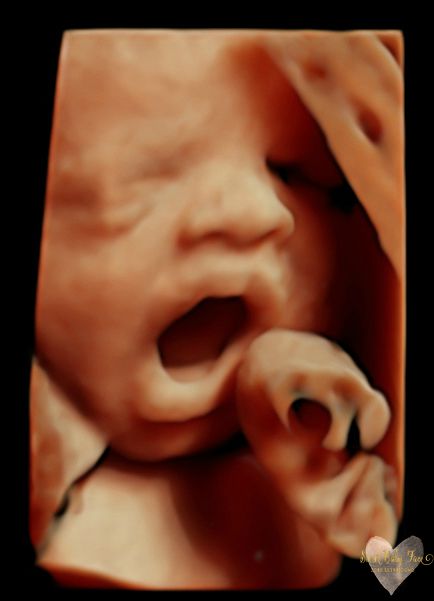

3D/4D/5D Ultrasound Gallery

Take a peek at our Photo Gallery. All of our 2D, 3D, 4D, HD elective ultrasound images are truly ours. They come directly off our machine from our highly trained staff. We can start getting great 3D/4D images as early as 10 weeks!